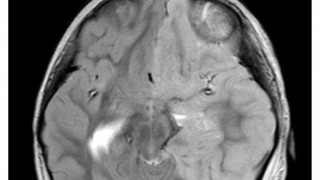

Qua khám và chẩn đoán hình ảnh, các bác sĩ thấy sợi dây chuyền có kích thước khá dài, đúc dạng xích nằm trong ổ bụng bệnh nhân.

Do vật thể là kim loại, có góc cạnh dễ gây biến chứng, các bác sỹ đã tiến hành gây mê để nội soi và gắp thành công sợi dây chuyền ra khỏi ổ bụng bé N.M.K.